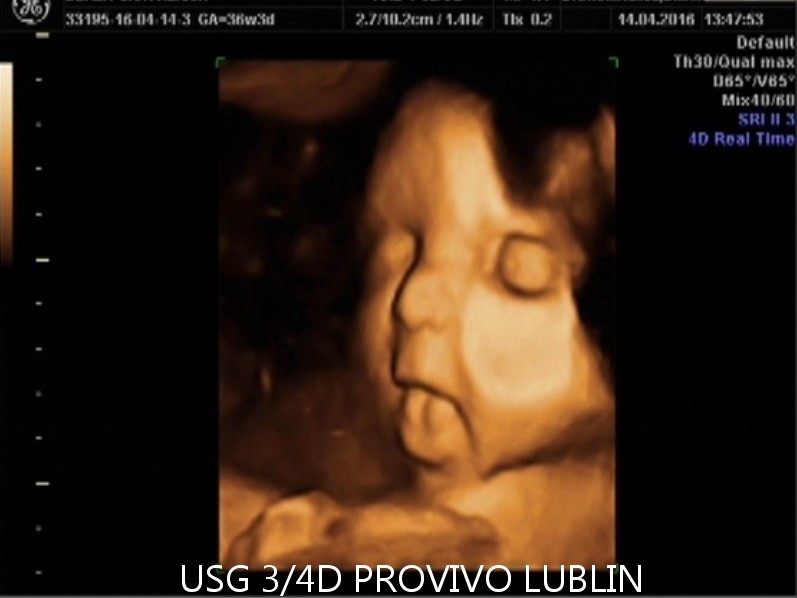

Urządzenia do USG 3D i 4D pokazują wyniki badania USG w sposób trójwymiarowy, dzięki czemu przyszli rodzice, zamiast jasnych i ciemnych plam na ekranie i zdjęciach, mogą zobaczyć swoje dziecko na żywo, zanim jeszcze pojawi się na świecie.

Aparaty do przeprowadzania USG 3D gwarantują trójwymiarową rekonstrukcję obrazu płodu i wnętrza macicy. Można w ten sposób zobaczyć powierzchnię zewnętrzną ciała rozwijającego się dziecka. Jego twarz ma dość wyraźny kształt, a rodzice, na pamiątkę badania, dostają zdjęcie z brzucha zapisane w formie elektronicznej na płycie CD.

USG 4D pokazuje obraz podobny jak w przypadku badania 3D, z tą różnicą, że jest to obraz dynamiczny, który zmienia się w czasie rzeczywistym. Przypomina to nieco podgląd na żywo, jak gdyby w macicy była umieszczona kamera.

Przyszli rodzice zobaczą w ten sposób ruchy dziecka, a także mimikę jego twarzy. Dla większości par jest to niezwykle wzruszająca chwili, kiedy po raz pierwszy mogą na własne oczy zobaczyć własne dziecko.